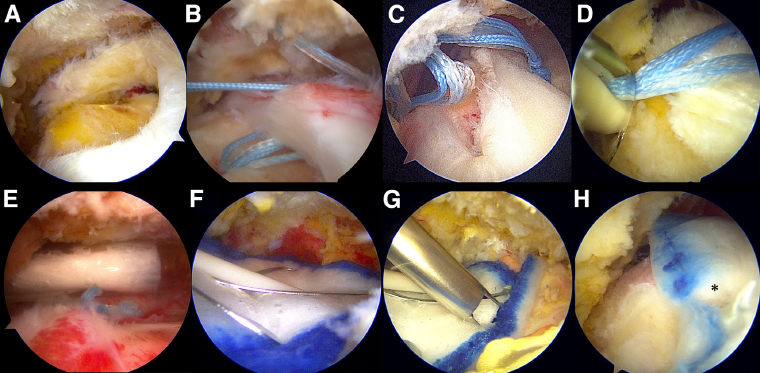

리제네텐은 생체유도성 콜라겐 임플란트로 관절내시경을 이용하여

손상된 회전근개 위에 콜라겐 패치를 덮어 조직이 자연스럽게 재생되도록 돕는 수술법입니다.

리제네텐은 파열된 회전근개 부위에 콜라겐 패치를 덧대어

새로운 힘줄 조직 성장을 지원하고,

약 6개월 이내 점진적으로 흡수되며 새로운 조직층으로 바뀌는 방식입니다.

파열된 힘줄 부위에

생체 유도성 콜라겐 패치 부착

부착만으로 조직의 치유를

유도하기 때문에 부담이 적음